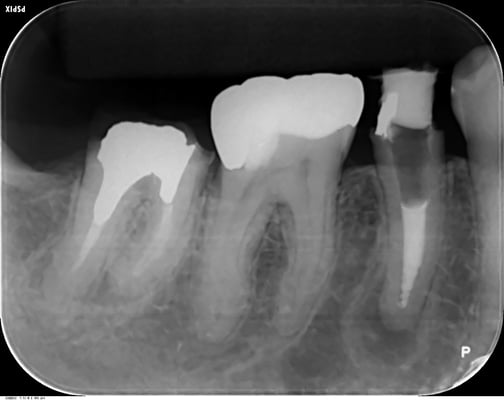

1年後

根尖の透過像も消失し、自覚症状(咬合痛などもありません)安心して最終印象採得(型どり)を行いました。

当院では、CTやレントゲンを撮影して悪い像(根尖などのX線透過像)が消失するのを確認してから補綴するようにしています。

透過像が残っているまま、治療を終了させるアメリカ的な合理主義的な考え方には断固として共感できませんね。